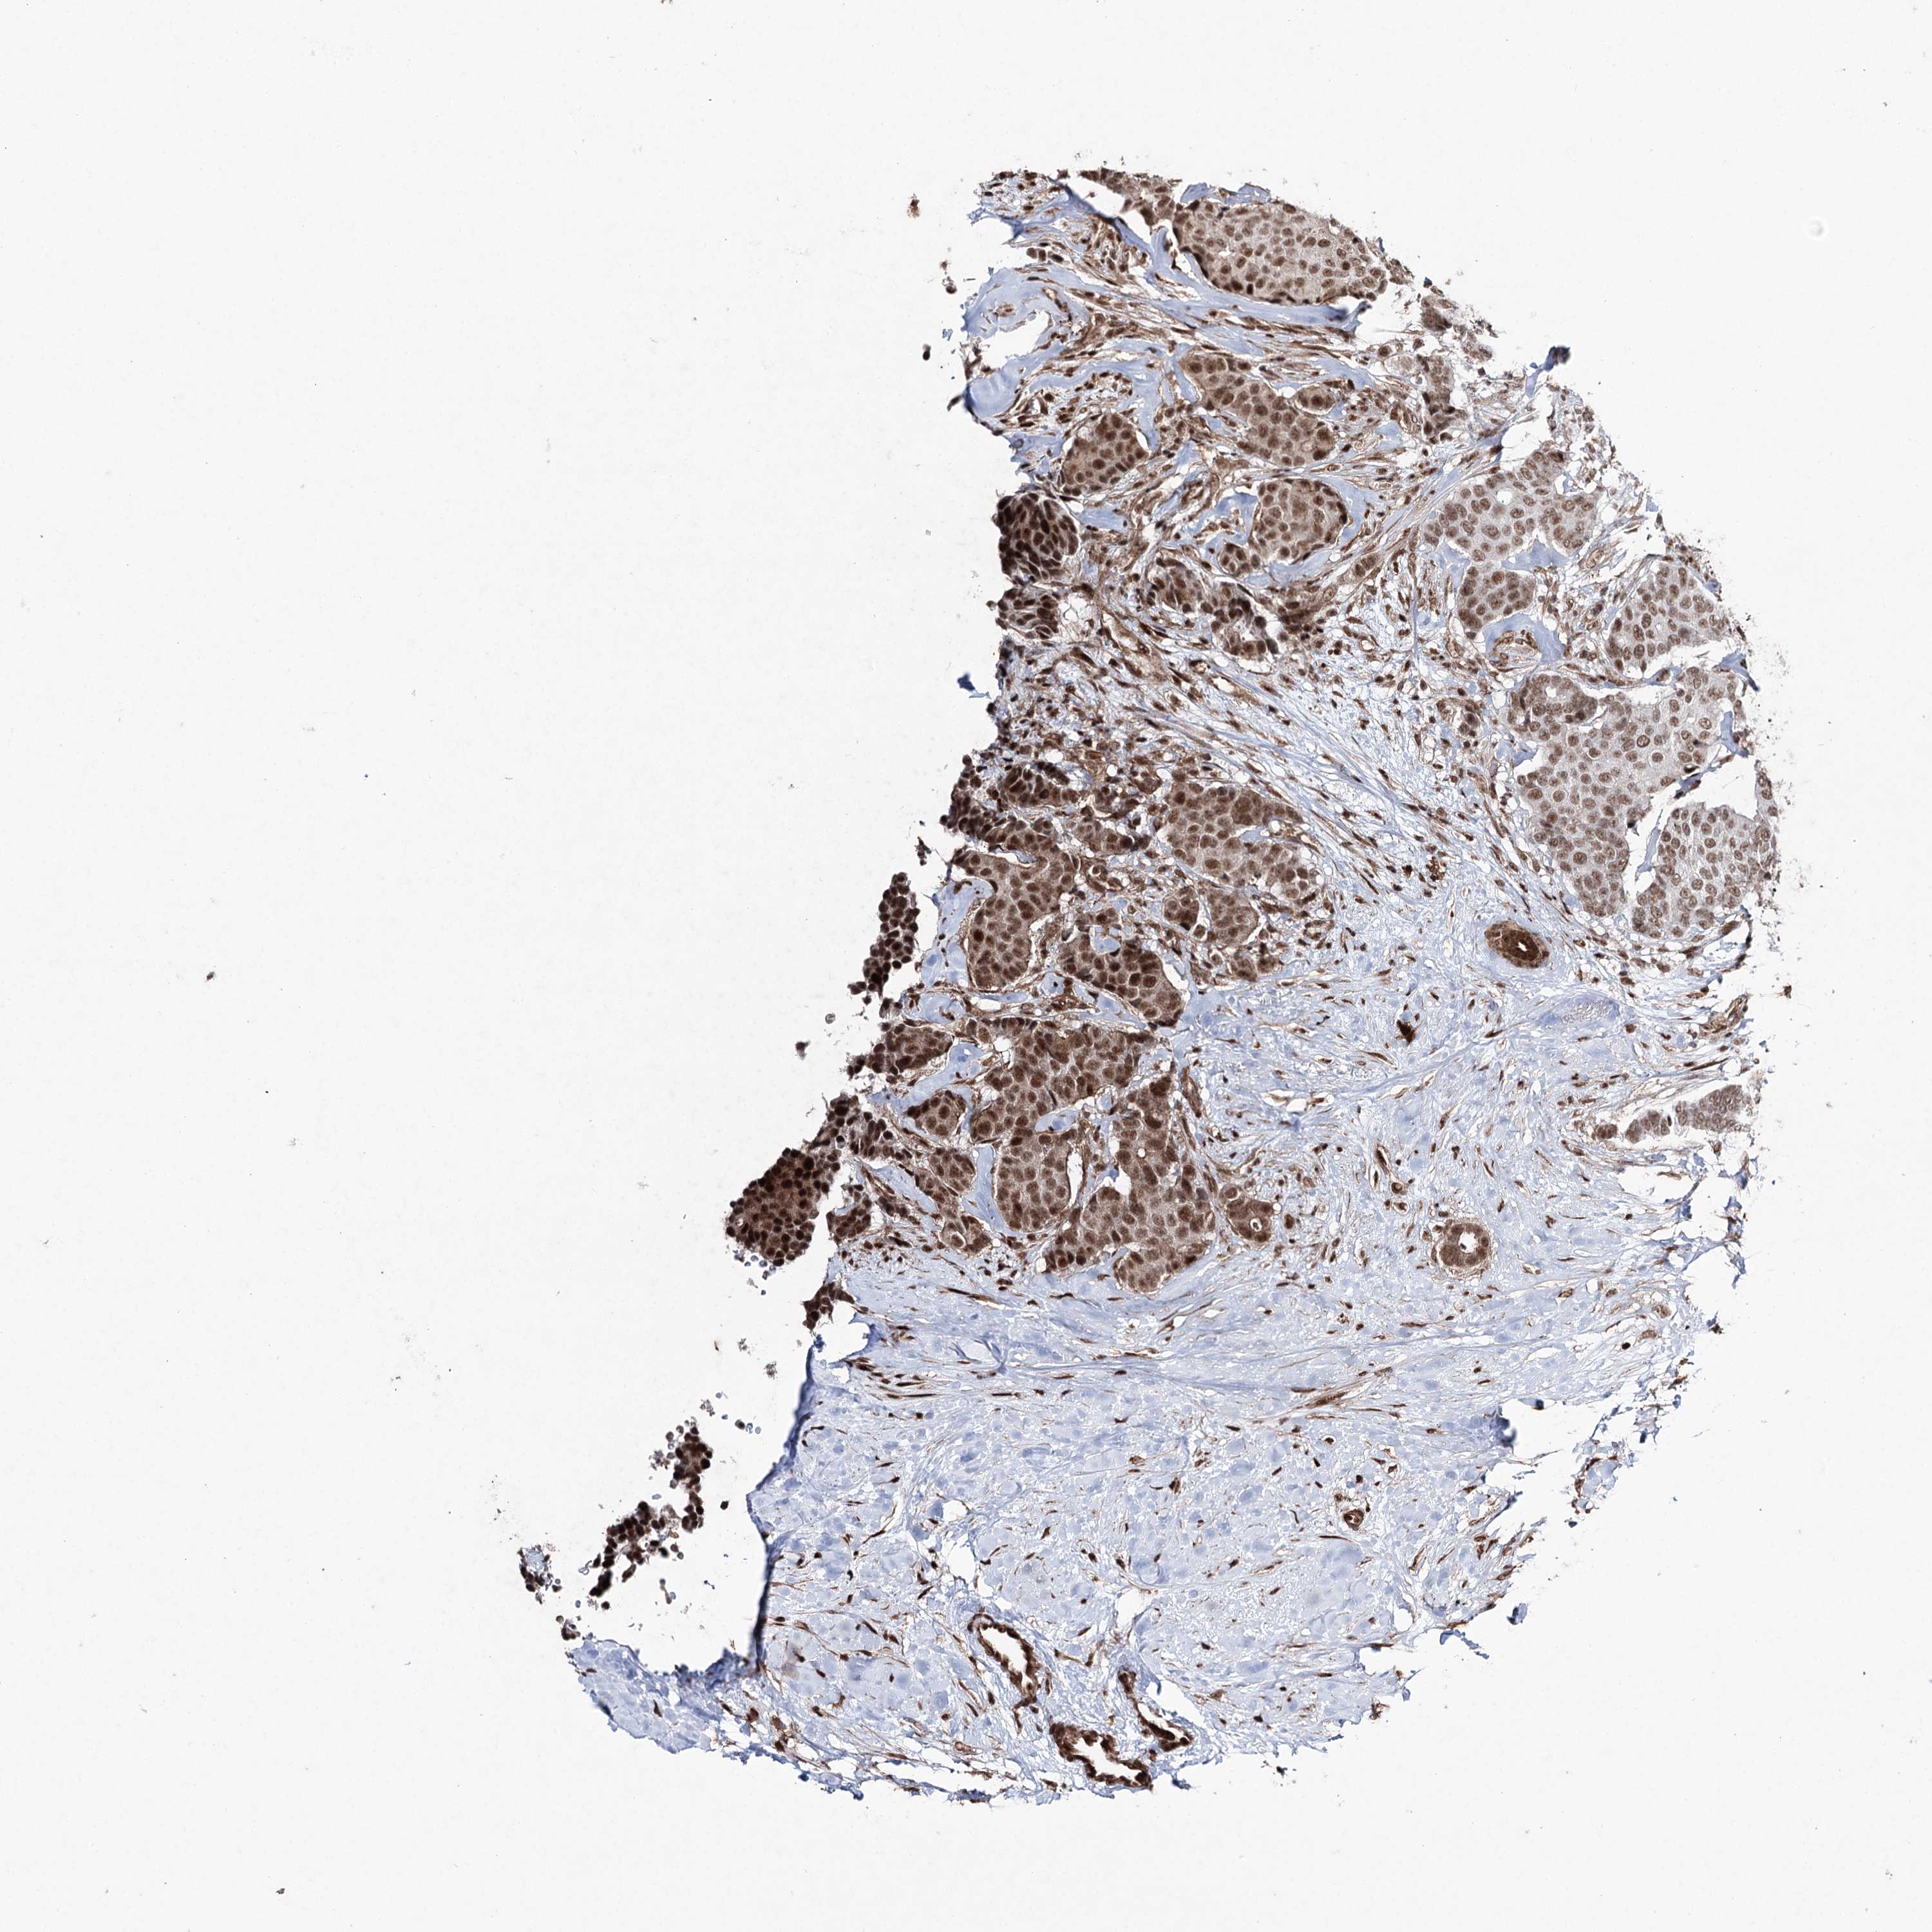

CANCER BREAST CANCER Show tissue menu

BRCA TCGA BRCA VALIDATION PROTEIN EXPRESSION